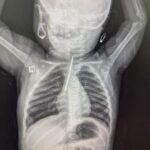

Next Article طفله في حوادث مستشفى كسلا تبلغ من العمر عشرة اشهر قامت بابتلاع مسمار و ثبت في ا…